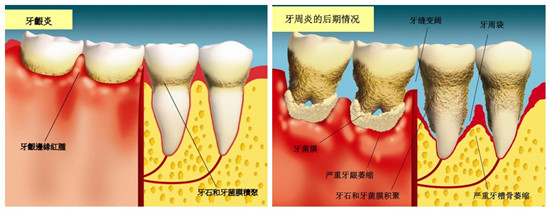

牙周病导致移位

三、牙周支持组织的破坏

牙齿在牙弓中的正常位置有赖于健康的牙周支持组织。牙周病患牙牙根周围牙槽骨吸收,支持组织减少,与该牙所受到的咬合力之间失去平衡,使牙齿向受力的方向移位。牙周肉芽组织也会使患牙伸长或移位。